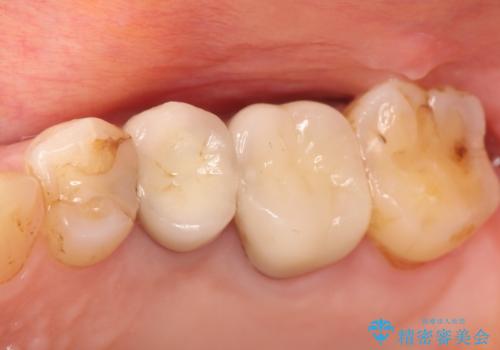

- 定期検診にて虫歯を見つけ、メタルボンドクラウンにて修復補綴治療を行なっております。

メタルボンドクラウンは内側に金属のフレーム、外側にセラミックを使用した被せ物です。